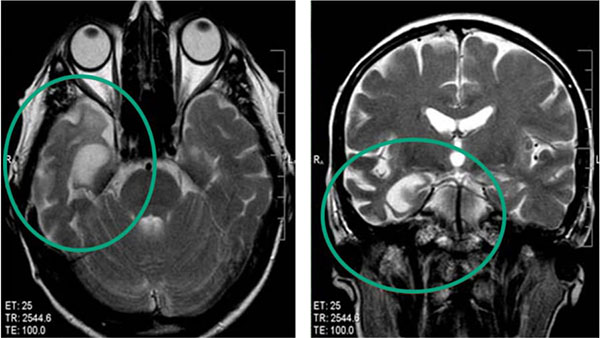

Vaši možgani se uničujejo prav zdaj — medtem ko berete te vrstice. Tudi rahlo povišan tlak oslabi krvne žile: izgubijo elastičnost, se zožijo in pokajo. Kri preneha dovajati kisik in hranila v možgane, brez njih pa živčne celice začnejo zadušiti in odmreti.